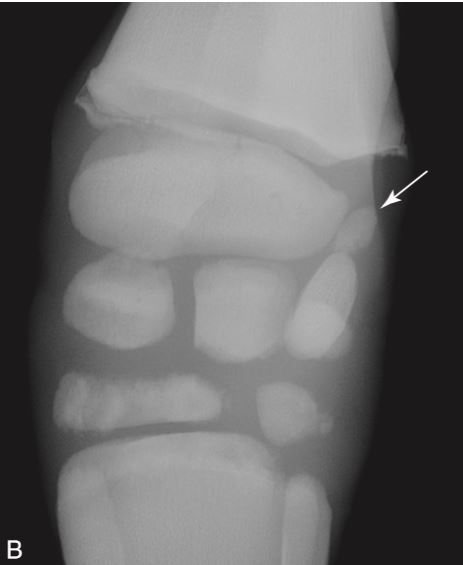

11

Q

Fusion of the distal radius and ulnar epiphysis should accord when?

A

3-6 months

The arrow is pointing to the ulnar epiphysis which is normally no fused in this horse at this age…there is incomplete ossification of the carpal bones in this horse.